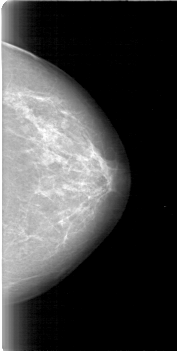

D_4011_1.LEFT_CC

LEFT_CC LINES 5251 PIXELS_PER_LINE 2641 BITS_PER_PIXEL 12 RESOLUTION 43.5 NON_OVERLAY